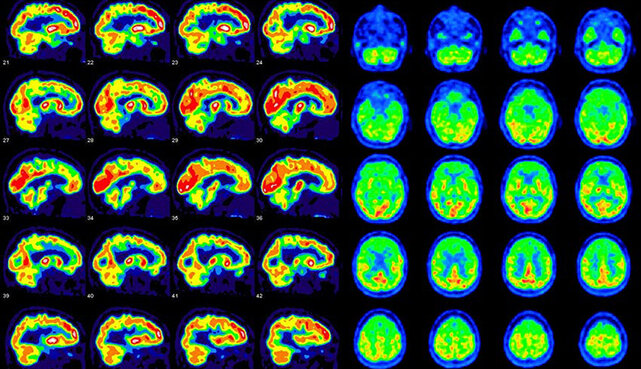

Для ПЭТ КТ его помечают углеродом 11. Этот радиофармпрепарат позволяет выявлять метаболические характеристики структурного поражения головного мозга. Главным показателем опухолевого процесса становится высокое накопление 11С -метионина в области, где располагается первичная опухоль. Диагностический метод позволяет отследить изменения в динамике, в том числе после проведения лечения. В месте где проходило лучевое иссечение опухоли, повышенное содержание препарата не отмечается, на участках некроза оно даже снижено.